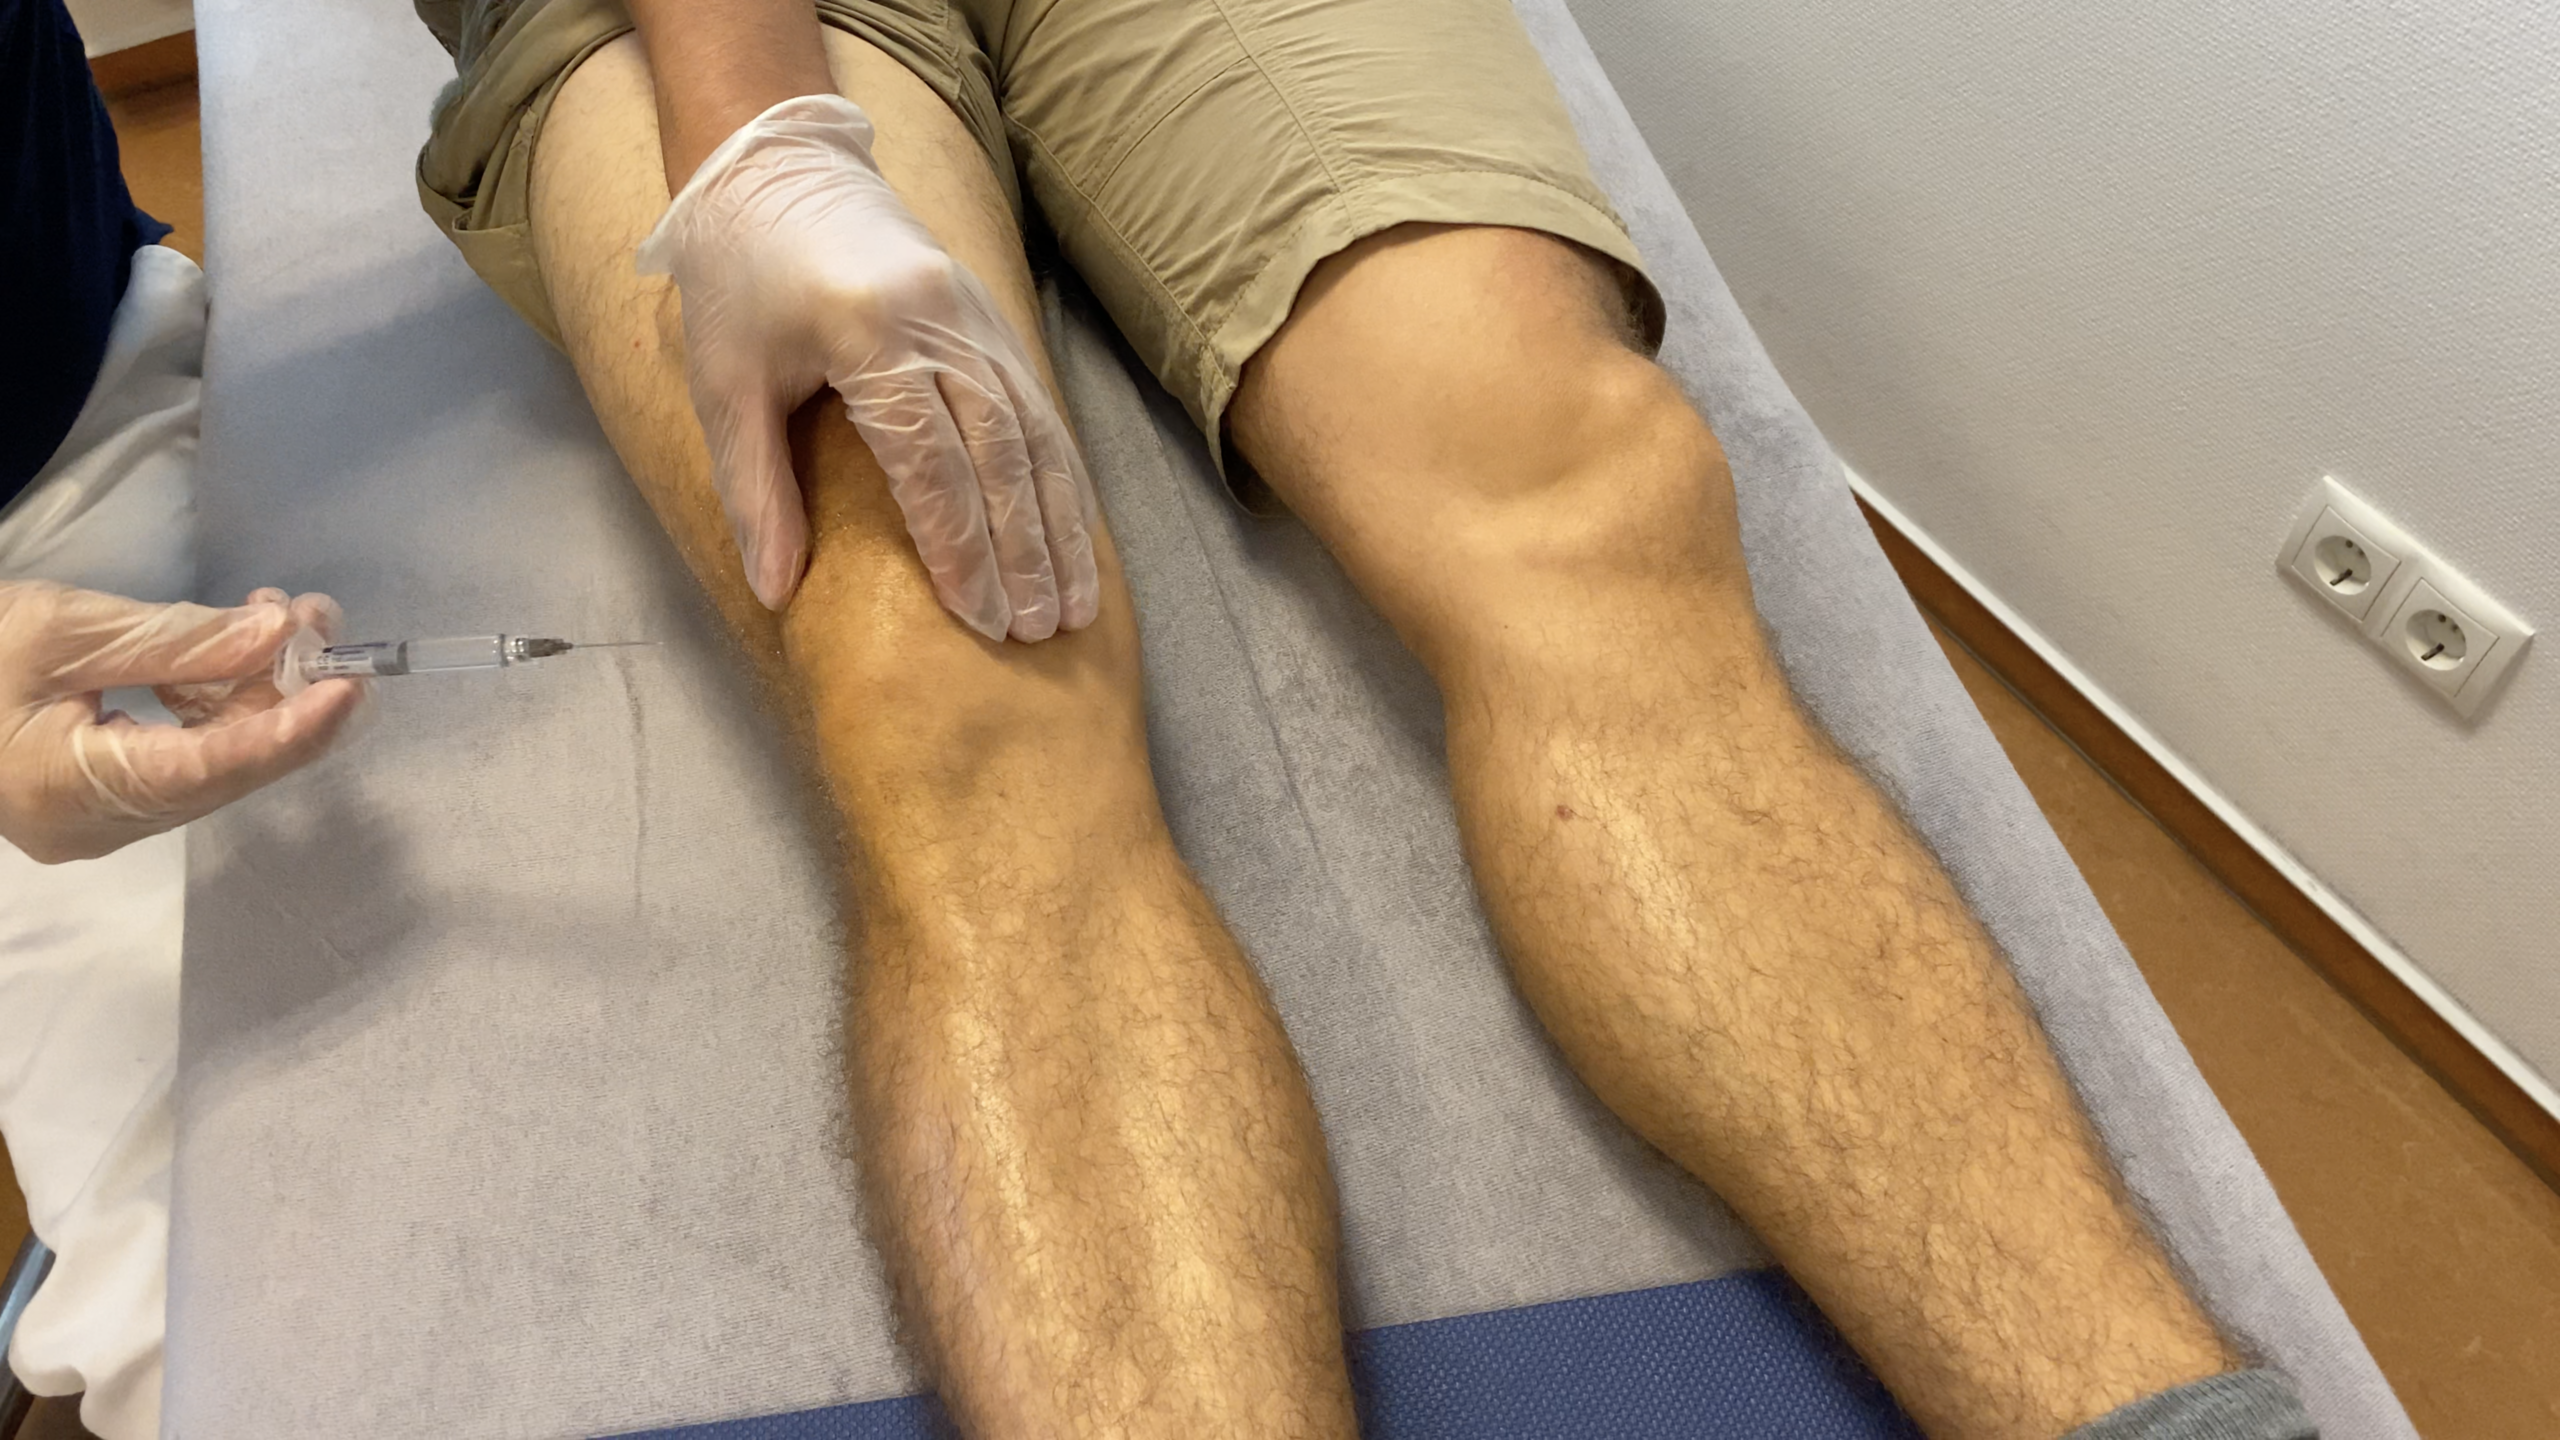

Neben Physiotherapeuten und Osteopathen entschied ich mich dazu, mir Hyaluronspritzen in das Kniegelenk geben zu lassen. Die muss man als Kassenpatient selbst bezahlen .

Es gibt unterschiedliche Qualitäten an Spritzen. Meine kosteten mich pro Spritze 50€. Es tat nicht weh. Das war komisch. Wie ein kleiner Stich. Nach der fünften Spritze sagte man mir, ich muss noch 2–3 Wochen warten, bis sich was tut. Es tat sich nichts. Geld verbrannt. Schade.